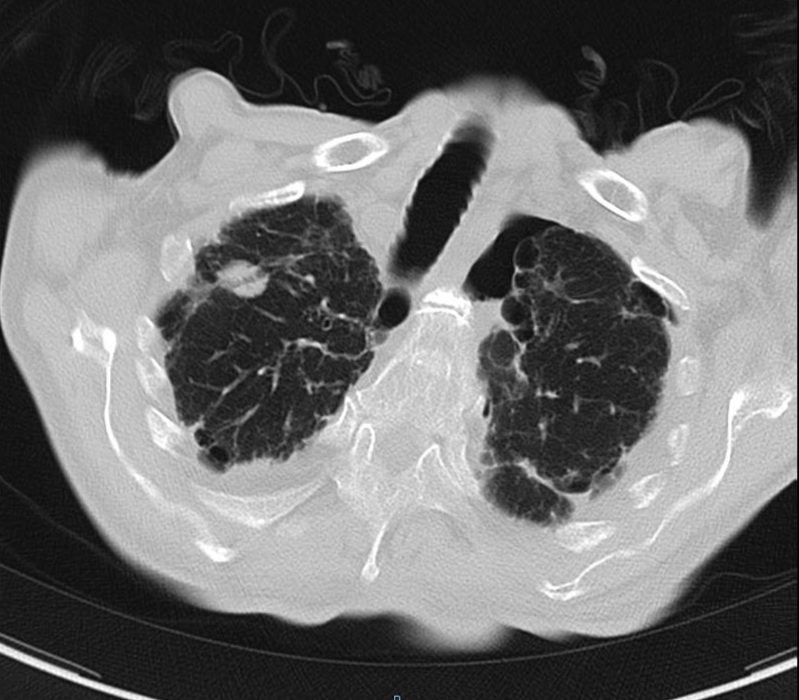

2020-08-31复查胸部CT:右肺结节影,结合病史考虑转移性病变,左侧局限性气胸,双肺气肿,双肺间质性病变,双侧胸腔积液;心脏增大,主动脉硬化。

△ 2020.08胸部CT